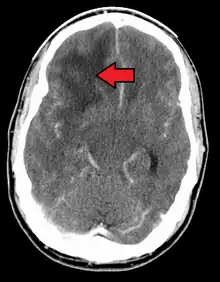

![]() | |

| Coronal MRI with contrast of a glioblastoma in a 15-year-old male | |